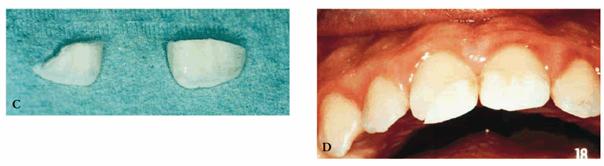

A male patient, 8 years, 3 months old.

PROBLEM: The patient presented with a supernumerary incisor and a double

tooth in place of the central upper left incisor (tooth #9) (Figures 27-11A and B). This anomaly manifests itself as a

structure resembling two teeth that have been joined together. In the anterior

region, the anomalous tooth usually has a groove on the buccal surface and a

notch in the incisal edge. Radiographs are necessary to determine if there is a

(fusion) union of the pulp chambers. Fusion exists when there is a joining of

two teeth by pulp and dentin. Two canals are usually present, as in this case.

Figure 27-11A and B: A supernumerary incisor and a double tooth in place of the central upper left incisor. Frontal and occlusal views.

TREATMENT: Both the supernumerary tooth and fused tooth were extracted (Figure 27-11C); also, the fixed orthodontic appliance was

applied to the maxillary arch to close the anterior diastema. Subsequently, the

incisal margin and the interproximal area of tooth #9 were restored to improve

esthetics (Figure 27-11D).

Figure 27-11C: Both the supernumerary tooth and fused tooth are extracted.

Figure 27-11D: An orthodontic appliance is applied to the maxillary arch to close the anterior diastema.

RESULT: The team work of several specialists created a good

morphic-functional recovery (Figures 27-11E and F) and an esthetic result that satisfied

the patient (Figures 27-11G and H).

Figure 27-11E and F: The morphic-functional recovery at the end of the orthodontic treatment.